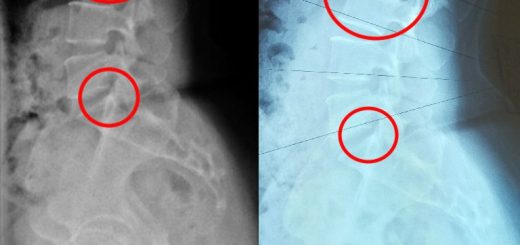

Shortness of Breath due to Hunching (Hyperkyphosis)